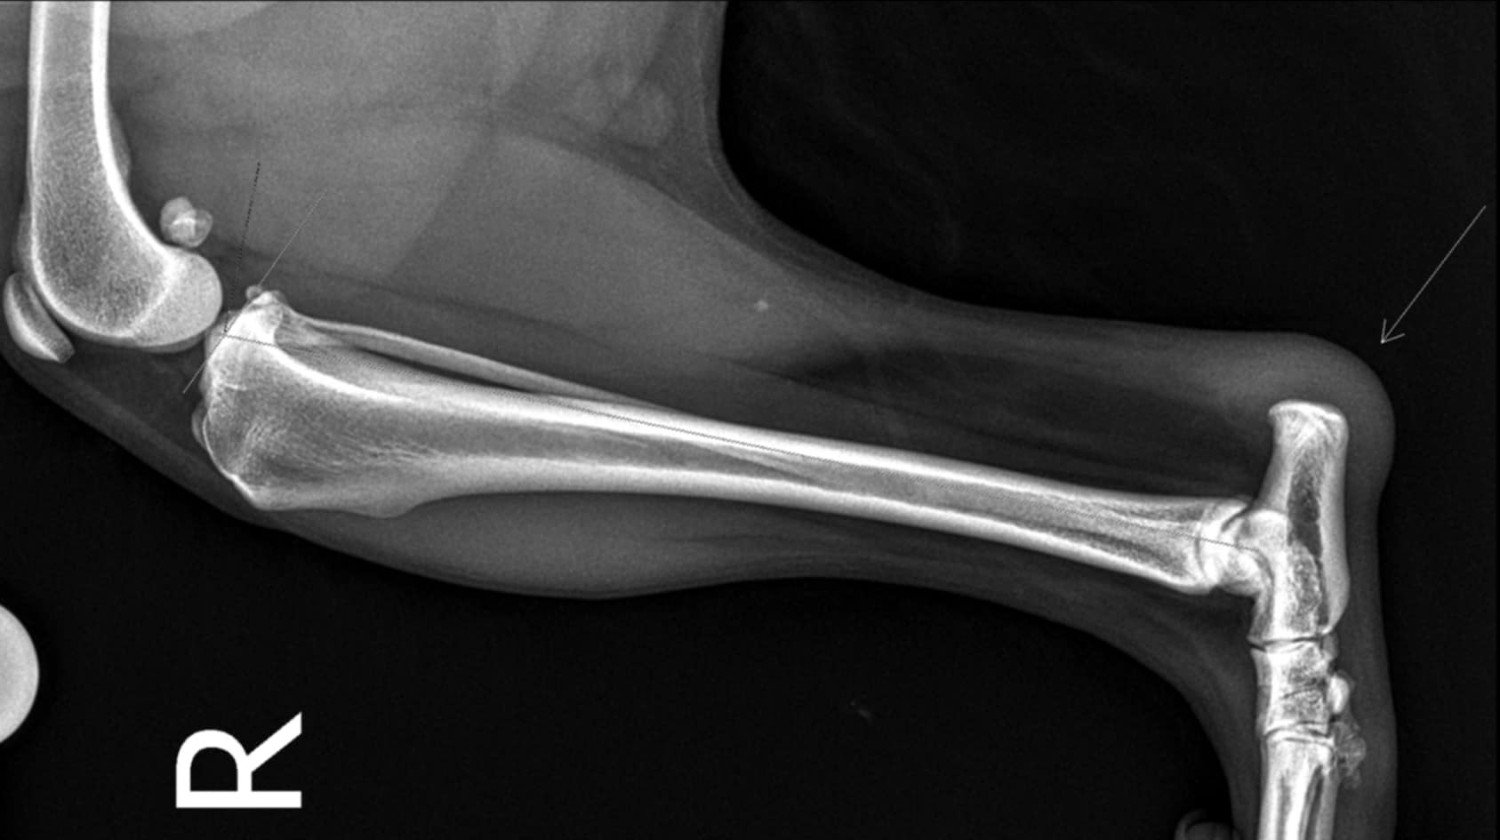

Sami wiecie, że serce ma większe niż kanapa, na której zaległ po ostatnich zmaganiach zdrowotnych z tylną łapką. Dlatego zrobię wszystko, żeby zapewnić mu maksymalnie dobrą i odpowiednią opiekę. Musimy wyleczyć stan zapalny ścięgna, które musiał sobie nadwyrężyć na jednym z naszych spacerów, których mi strasznie aktualnie brakuje!

Kilka wizyt u weterynarza i garść rachunków później, hajsik z wakacji poszedł w łapy Ozika, a my jesteśmy w miejscu, gdzie fizjoterapia to nasz game changer.

Nasze psie SPA i fizjo odbywa się u cudownych dziewczyn z Psijaciel – groom & rehab w Bochni – polecam i ja i mój futrzaty psijaciel z całego serca ❤️